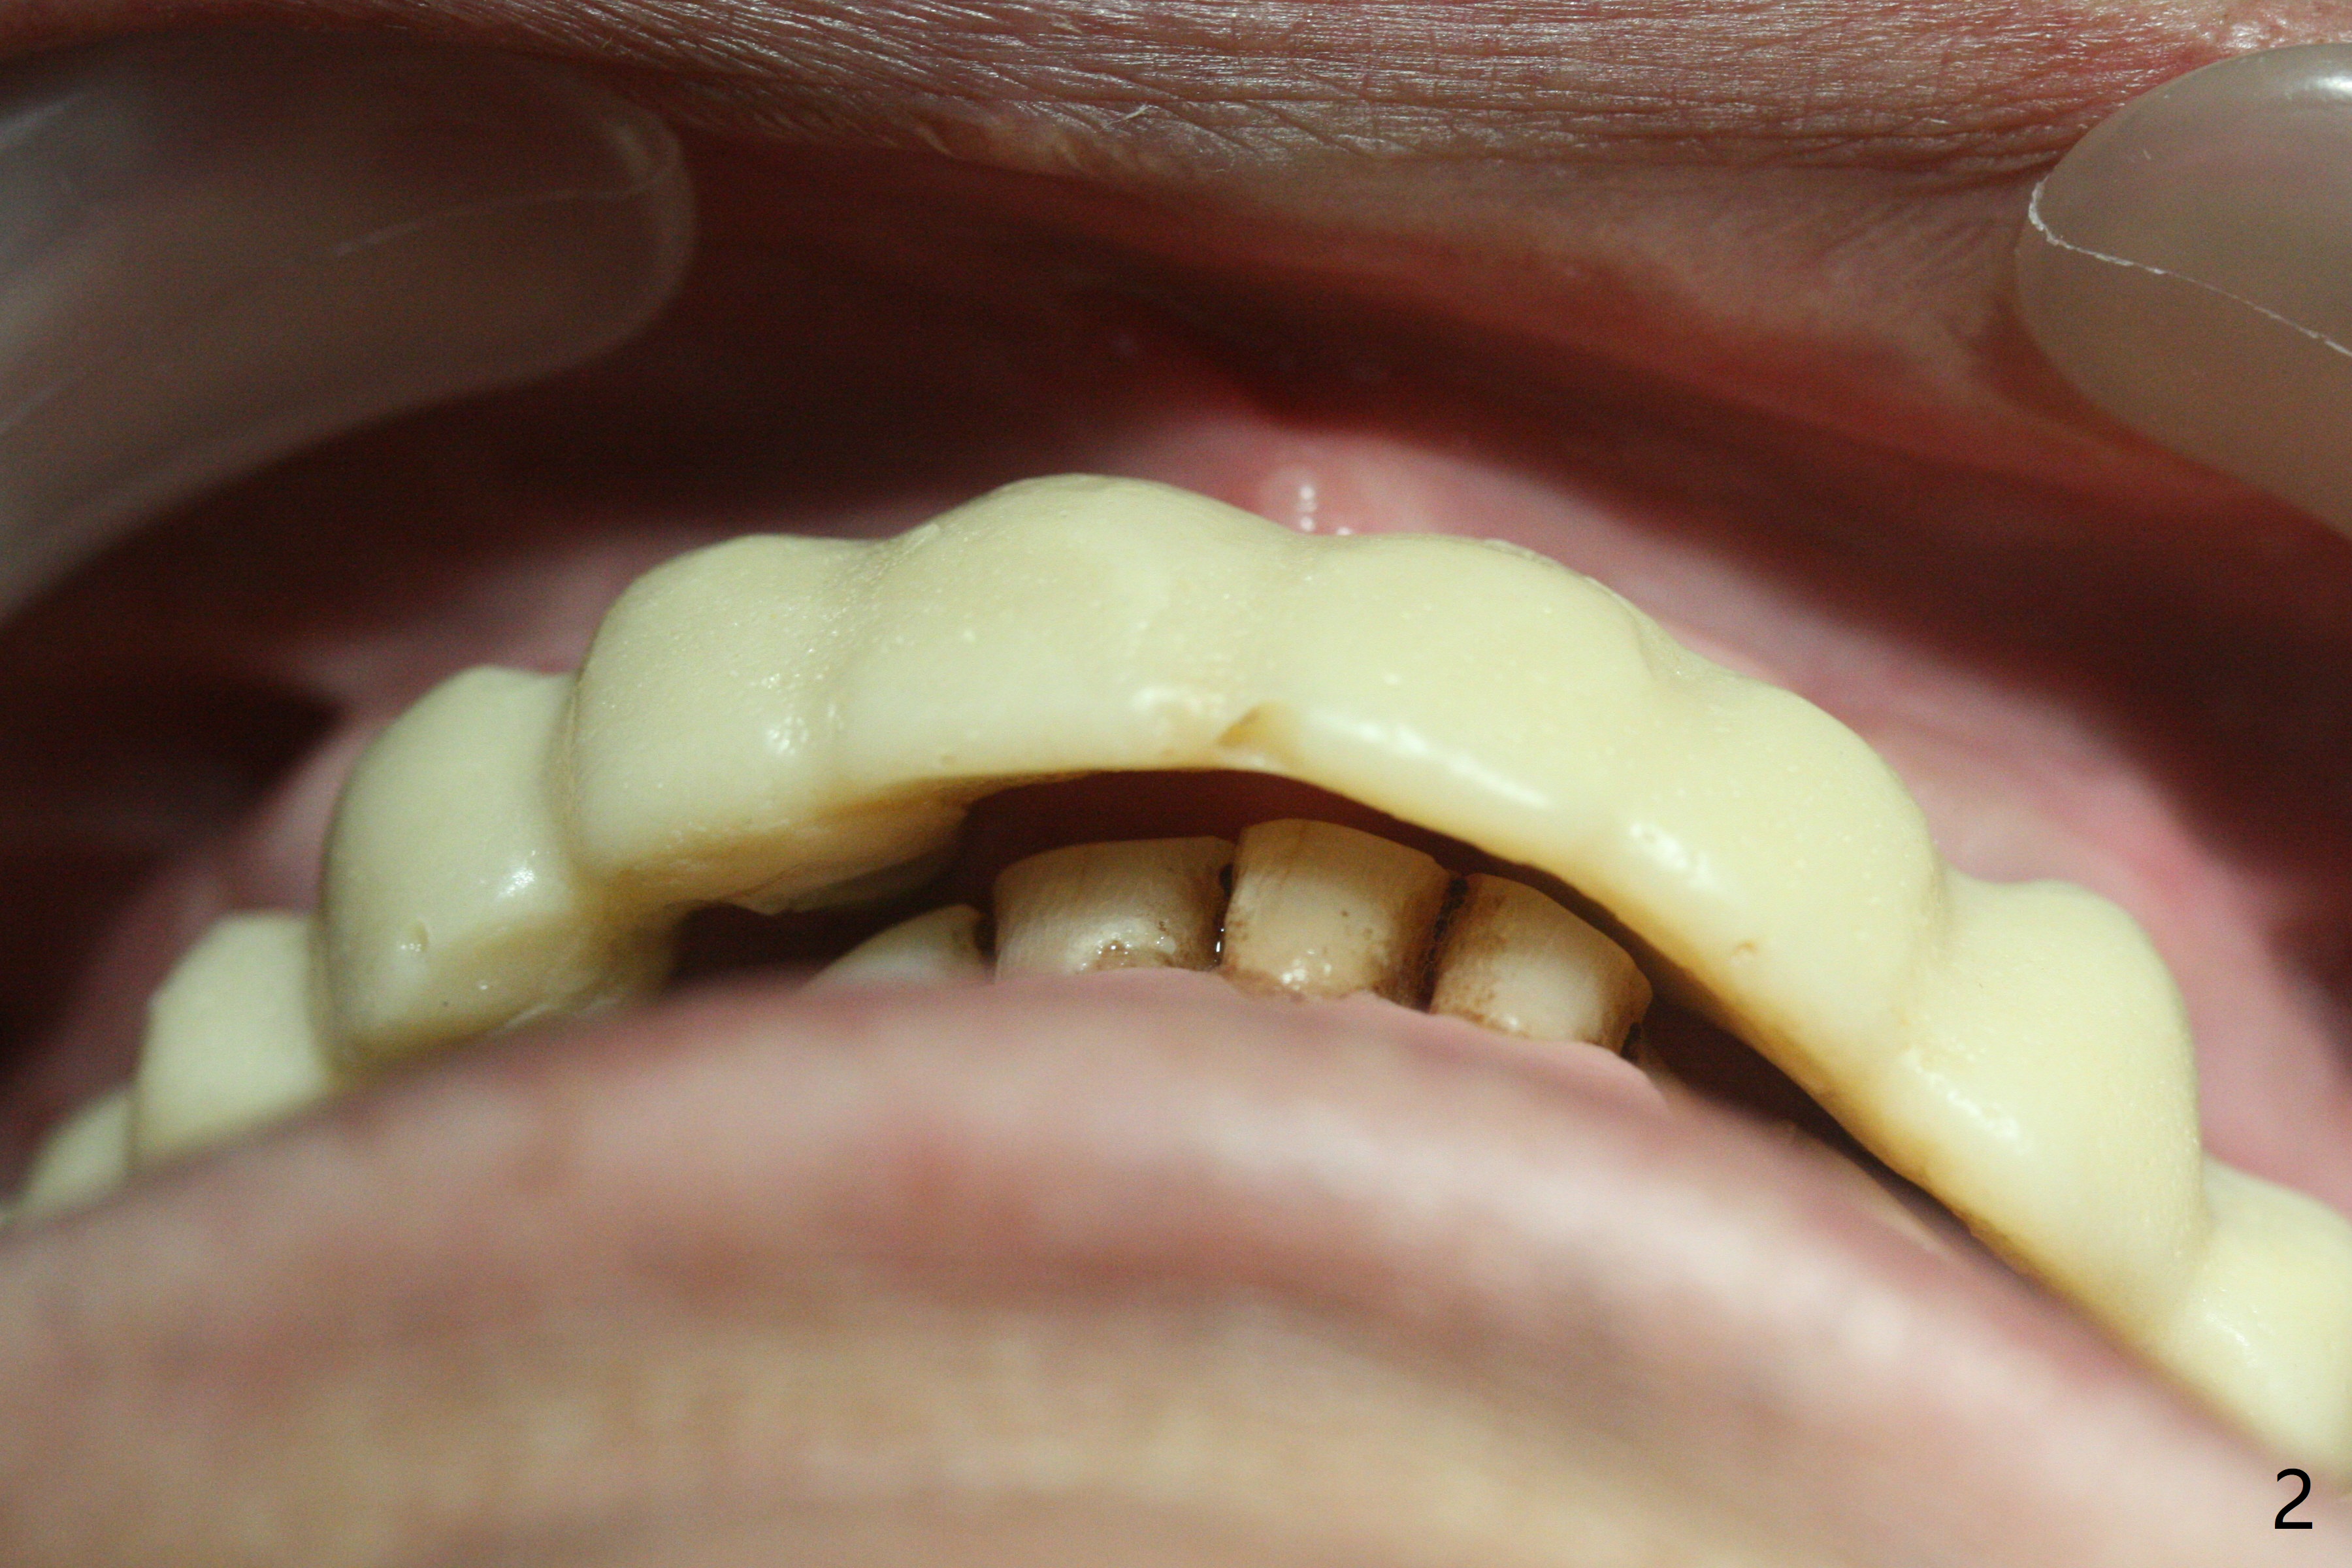

With temporarization of #3,4,13-15 (Fig.1), the anterior clearance is maintained (Fig.2). When provisional is removed, there is no papilla between #7 and 8 (Fig.3,4). After confirmation of complete seating of the abutments at #6 and 10 (Fig.5,6), gingivectomy is conducted with Diode laser (Fig.7,8). Following provisional being relined and modified, the anterior papillae form (Fig.9).